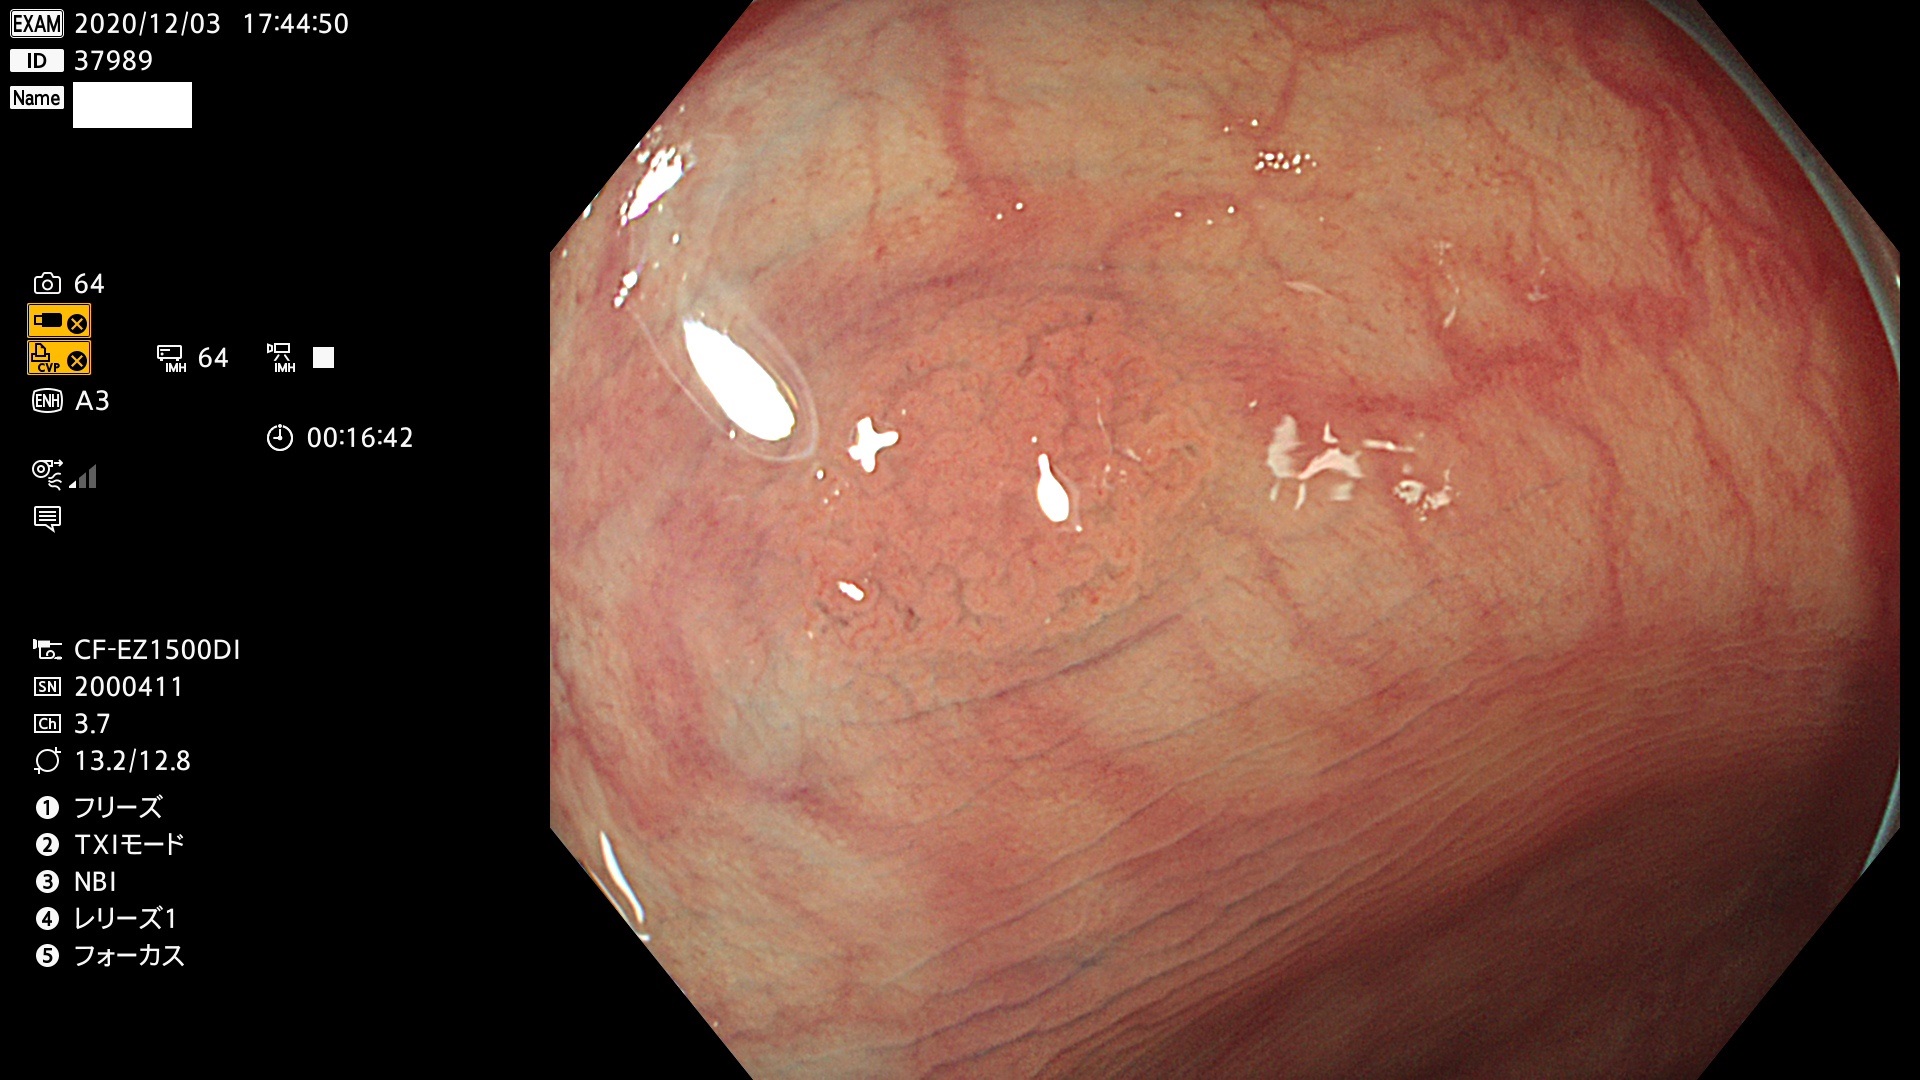

37900 37902 37903 37904 37905 37906 37907 37909 37910 37911 37912 37913 37914 37915 37916 37917 37919 37921 37922 37923 37926 37928 37929 37930 37931 37933 37934 37935 37936 37937 37938(SSAPのみ) 37939 37940 37941 37942 37943 37946 37947 37948 37949 37951 37952 37953(SSAPのみ) 37955 37956 37957(SSAPのみ) 37958(SSAPのみ) 37960 37962 37963 37964 37966 37967 37968 37971 37972 37973 37975 37976 37977 37979 37982 37983 37984 37985 37986 37987 37988 37989 37990 37991 37992 37993 37994 37995 37996 37998 37999

発見困難で危険性の高い平坦型病変(上記100名より抽出)